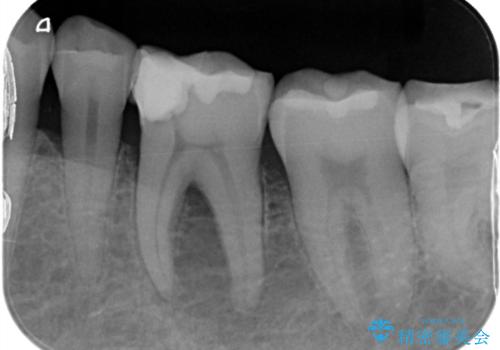

【根管治療】物が当たるだけで痛い